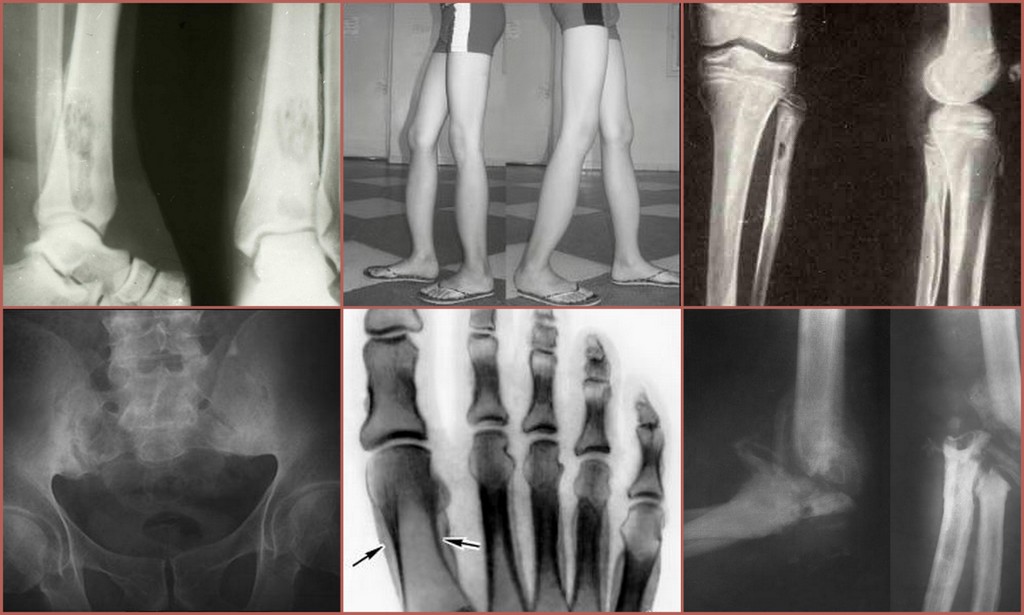

Раздел: Альбом открытий